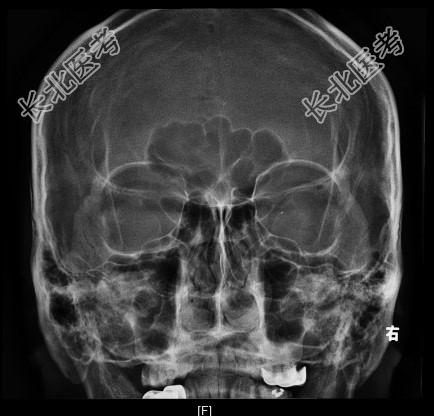

- [材料题] 患者男性,4岁,以“右眼外伤后视物不清8天”为主诉入院。眼部检查:右眼视力指数/0cm,左眼视力.0。右眼混合充血,角膜透明,KP(+),6点钟方位角膜缘可见2mm裂伤口,已闭合;前房中等深度,房水闪光(+);虹膜表面纹理清晰,无前后粘连,6点钟方位可见穿通孔;瞳孔圆,直径3mm;晶状体混浊;眼底无法窥视。左眼未见明显异常。眼眶X线检查结果见图155,CT检查结果见图156(平扫)和图157(三维成像)。

图157。